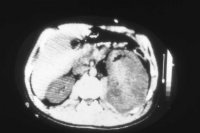

Von Wichtigkeit sind die bildgebenden Verfahren: Sonographie, CT bzw. AUR.

Beispielhaft die Darstellung eines ausgedehnten Nierenabszesses in Sonographie, CT und AUR (Abbildung 6).